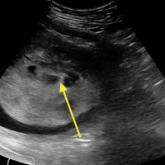

ArticleDiagnosis at a Glance: Partial Hydatidiform Molar PregnancyAuthor:Nadia Maria Shaukat, MD, RDMS, FACEPPublish date: January 11, 2017A 26-year-old gravida 3, para 2-0-0-2, aborta 0 whose last menstrual period was 15 weeks 5 days, presented to the ED with complaints of mild vagina...Read More